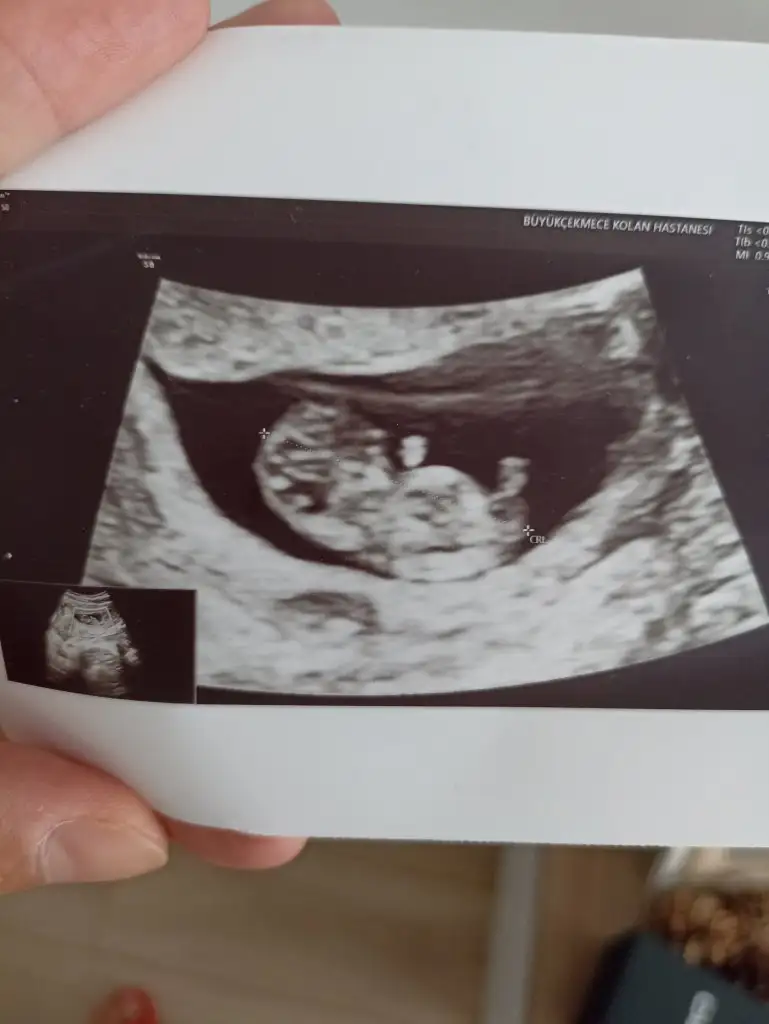

6+1 ve 7+1 i de görmek isterim kaçıncı sayfada hatırlıyor musunuz?Çok teşekkür ederim.Eller kollar hareketlenmiş bir de. Öyle görünce içim kıpır kıpır oldu.Bir kızım var bir de oğlum olsun isterim.Ama kız olursa da cok mutlu olurum.Gercekten hiç fark etmez. Evlat sonuçta Rabbim hayırlısı neyse sağlıklı bir şekilde onu nasip eder inşallah.Kızıma hamileyken rüyamda kız olacağını görmüştüm.Bunda bebek gördüm ama cinsiyetini görmedim.@lolaylty 6+1 ve 7+1 ultrason görüntüsüne göre erkek demişti siz de kız dediniz.Hangisi olacak bakalım Hayırlısı olsun.Rabbim sizin bebeğinizi de gönlünüze göre sağlıklı bir sekilde kucağınıza almayı nasip eder inşallah.

Vajinal ultrasonda çekilmişti.6+1 ve 7+1 i de görmek isterim kaçıncı sayfada hatırlıyor musunuz?